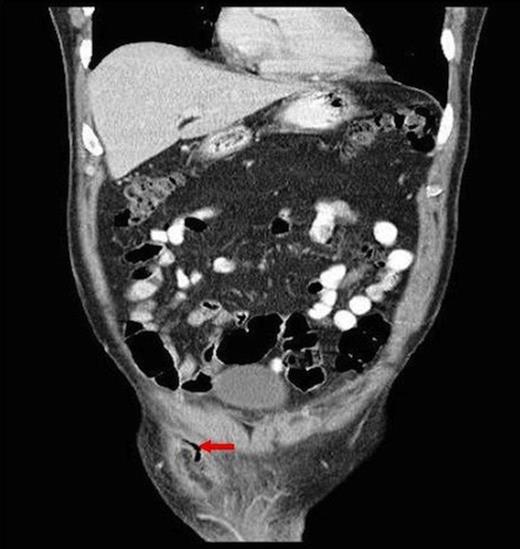

Coronal CT showing descent of appendix segment into scrotum and associated fat stranding

CT has 18 – 97% sensitivity and near 100% specificity and up to 98% accuracy in diagnosing intra-abdominal appendicitis leading to reduction in negative appendicectomies from 22% to 14% and identification of concurrent pathology in 51% in one series (3). The most common CT findings are that of enlarged appendix with surrounding fat stranding (93%) which is similar to our case (4) (Fig. 2). The only other reported pre-operative detection of appendicitis within a hernia was also diagnosed by CT (5). CT is becoming increasingly available without harmfully delaying surgery and can direct surgical approach.

Primary acute appendicitis is thought to be caused by intra-luminal congestion and inflammation. Appendicitis within herniae is thought to be caused by extra luminal constriction by the hernia neck. The mesh provides another aetiological possibility. There is only one report of acute appendicitis related to hernia repair 18 months prior where the inflamed appendix was adherent to peritonealised mesh. The authors’ postulate appendicitis could have been caused by mesh irritation or appendix adherence to mesh with subsequent kinking leading to inflammation, or primary acute appendicitis which adhered to the old mesh site (8). The demarcation of acute appendicitis in the distal segment in this case suggests appendix entrapment as it had passed into the scrotum or adherence to the medial border of the non-peritonealised exposed mesh (Figure 2).